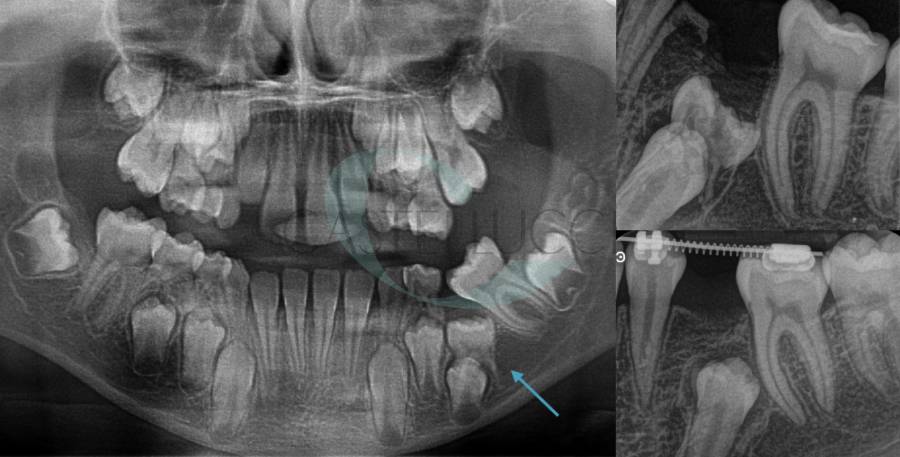

• Terapia chirurgica degli elementi dentari decidui con ritardo di permuta

• Disinclusione chirurgica degli elementi dentari permanenti ritenuti